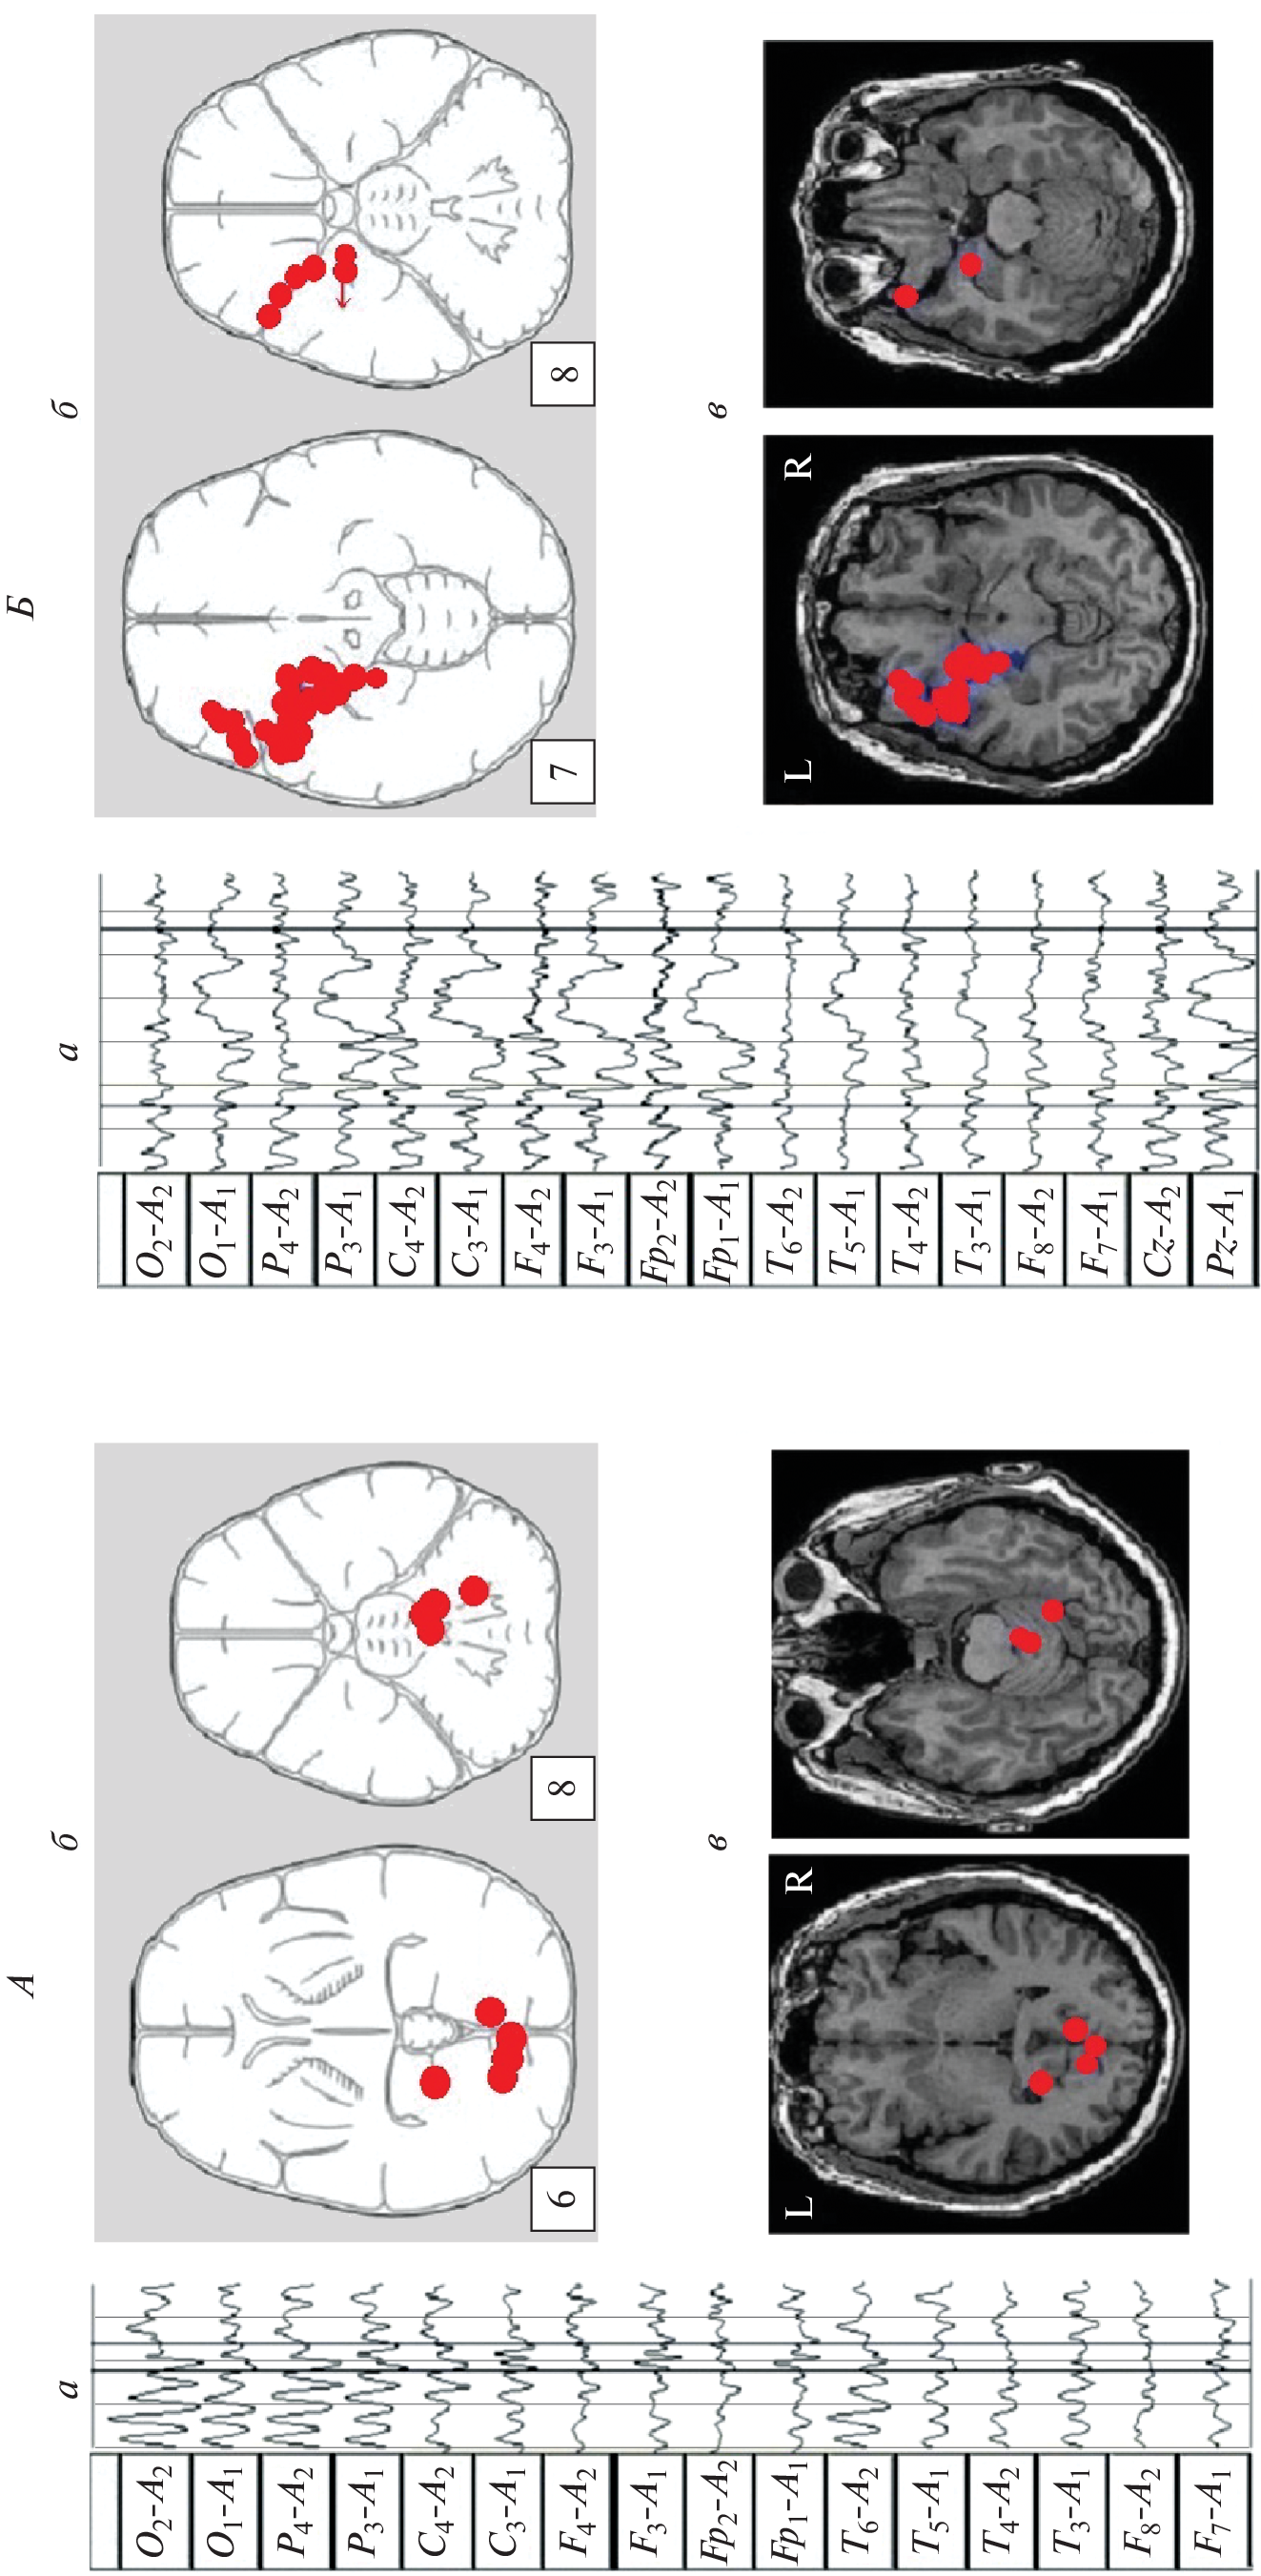

We studied the features of EEG and visual memory processes in 27 patients with a mediobasal regions extracerebral tumor of right and left hemispheres. According to neuroimaging (MRI) and morphometry, the degree of hippocampus involvement in pathological process was assessed. The predominant concentration of irritative-epileptiform signs in the affected hemisphere, as well as the presence of atypical alpha-rhythm episodes in the tumor projection zone, were classified as EEG markers of tumor compressive effect on the hippocampus. Signs of non-identical involvement of the right and left hippocampi in the pathological process were found in the form of a predominance of irritative signs in the left hemisphere throughout the group as a whole. Equivalent dipole sources (EDS) of atypical alpha rhythm are more confined to hippocampal structures than irritative EEG patterns. Neuropsychological testing of visual memory did not reveal significant disturbances in memory processes at this stage of the disease.

- Коптелов Ю.М., Гнездицкий В.В. Анализ “скальповых потенциальных полей” и трехмерная локализация источников эпилептической активности мозга человека // Журн. неврол. психиатр. им. С.С. Корсакова. 1989. Т. 89. № 6. С. 11. Koptelov Yu.M., Gnezditskii V.V. [Analysis of scalp potential fields and the three-dimensional localization of sources of epileptic activity in the human brain] // Zh. Nevrol. Psikhiatr. Im. S.S. Korsakova. 1989. V. 89. № 6. P. 11.

- Болдырева Г.Н. Атипичные формы церебральной альфа-активности при поражении регуляторных структур мозга человека // Физиология человека. 2018. Т. 44. № 3. С. 14. Boldyreva G.N. Atypical forms of cerebral alpha activity when human brain regulatory structures are damaged // Human Physiology. 2018. V. 44. № 3. P. 246.

- Верхлюдов В.М., Щучкин Е.В., Ушаков В.Л. и др. Оценка локализации дипольного момента источников альфа- и тета-ритмов ЭЭГ с использованием кластерного анализа в норме и у больных шизофренией // Журн. высш. нерв. деят. им. И.П. Павлова. 2006. Т. 56. № 1. С. 47. Verkhlyutov V.M., Shchuchkin Yu.V., Ushakov V.L. et al. [Estimation of localization and dipole moment of alpha- and theta-rhythm sources by cluster analysis in healthy subjects and schizophrenics] // Zh. Vyssh. Nerv. Deiat. Im. I.P. Pavlova. 2006. V. 56. № 1. P. 47.

- Болдырева Г.Н., Шарова Е.В., Коптелов Ю.М. и др. Исследование генеза патологических паттернов ЭЭГ при опухолевом и травматическом поражении мозга человека // Физиология человека. 2005. Т. 31. № 1. С. 24. Boldyreva G.N., Sharova E.V., Koptelov Yu.M. et al. Study of the genesis of pathological EEG patterns in tumor and traumatic lesions of the human brain // Human Physiology. 2005. V. 31. № 1. P. 18.

- Фролов А.А., Болдырева Г.Н., Коптелов Ю.М. Поиск источников патологической альфа-активности ЭЭГ человека при поражении лимбических структур // Журн. высш. нерв. деят. им. И.П. Павлова. 1998. Т. 48. № 4. С. 687. Frolov A.A., Boldyreva G.N., Koptelov Yu.M. [Sources of pathological EEG alpha-activity in patients with lesions of limbic structures] // Zh. Vyssh. Nerv. Deiat. Im. I.P. Pavlova. V. 48. № 4. P. 687.